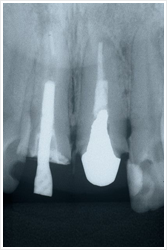

無理な場合とは、こんなときです。

・ 病巣が大きすぎて歯の中からだけでは(神経のあった細い管からだけでは)膿を全部出し切れない場合

・ 根の形が極端に曲がっていて、通常の治療が困難な場合

・ 炎症病巣をもつ歯に強固な差し歯が装着されていて、その差し歯を壊せない(除去できない)と予想される場合

・ 炎症病巣をもつ歯に高価なかぶせ(冠)や差し歯が装着されていて、その冠を壊したくない場合

などです。

実際の治療はこんな感じです。